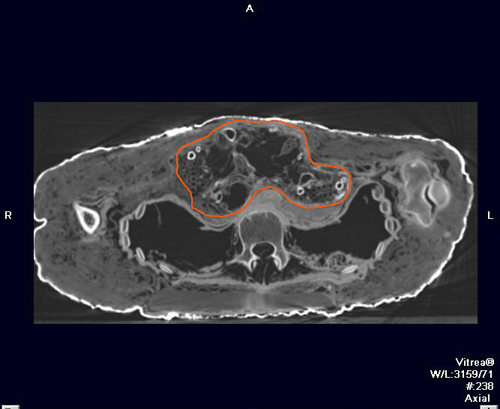

使用专业分析技术检查木乃伊画像,动图截自Giacomo Chiari的视频。作品信息:《一个大胡子男士的木乃伊肖像画》,大约公元150-170年,热蜡绘画。The J. Paul Getty Museum,74.AP.11,现展出于盖蒂别墅210陈列室。